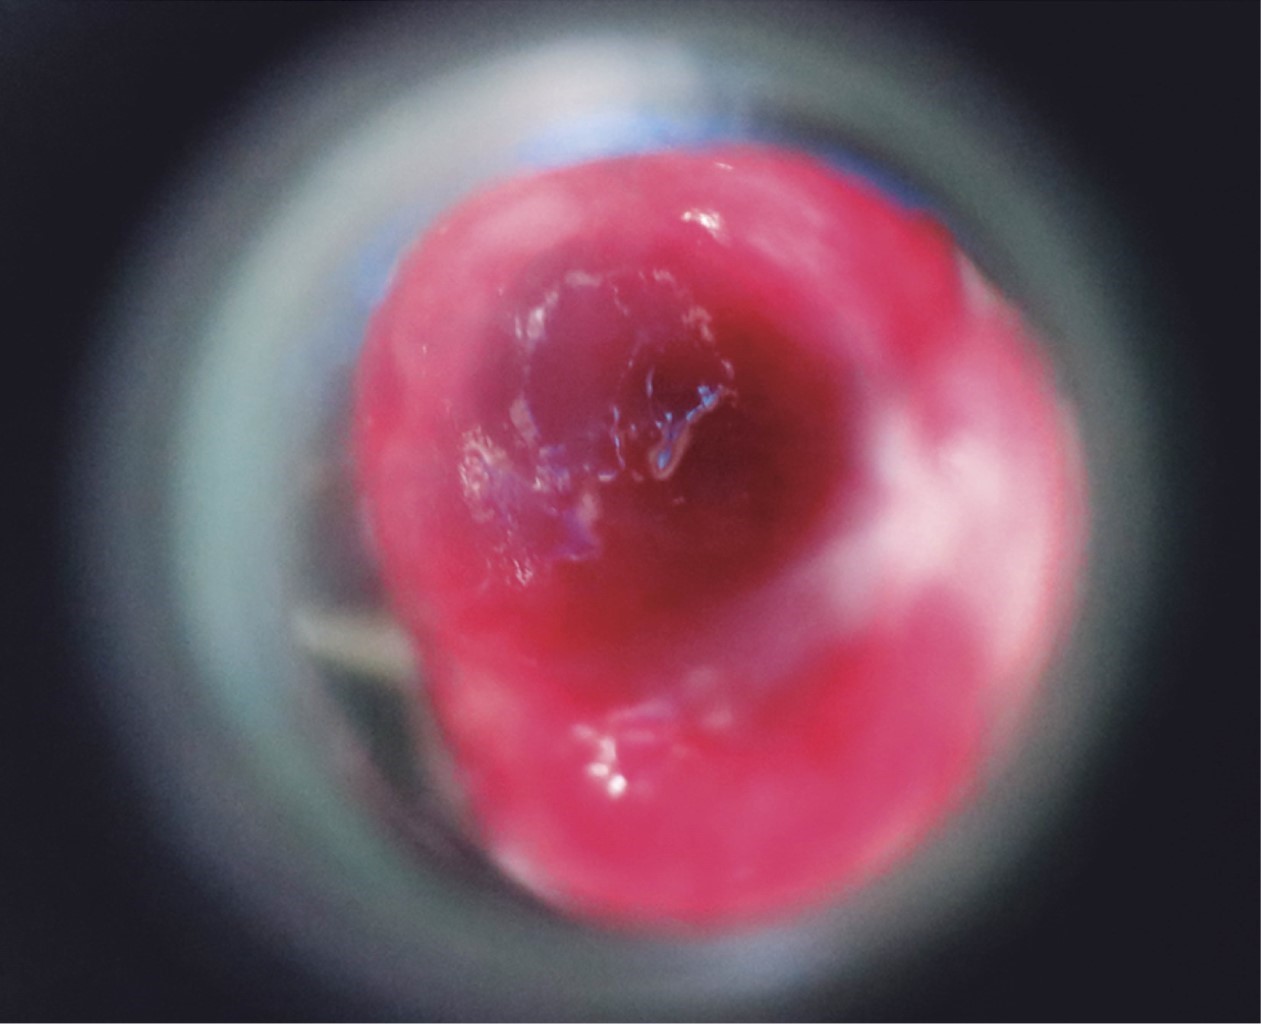

Se trata de un paciente del sexo masculino, de 30 años de edad, soltero, originario y residente de la Ciudad de México, quien acude por una dermatosis localizada a tronco, del que afecta área genital, y de ésta el prepucio del lado derecho. Dermatosis constituida por una neoformación de 3 × 1.5 × 1 cm, de aspecto vascular, eritematosa, pediculada, simétrica, de bordes regulares bien circunscritos, de superficie lisa brillante, con algunas áreas blanquecinas y algunas exulceraciones. De evolución aguda y dolorosa (Figuras 1 y 2). El resto de la exploración de piel, anexos y la revisión física general, sin alteraciones.

El estudio dermatoscópico mostró áreas eritematosas homogéneas, líneas blancas en riel, líneas irregulares vasculares y vasos polimorfos (Figura 3).

Figura 1

Figura 2

Figura 3